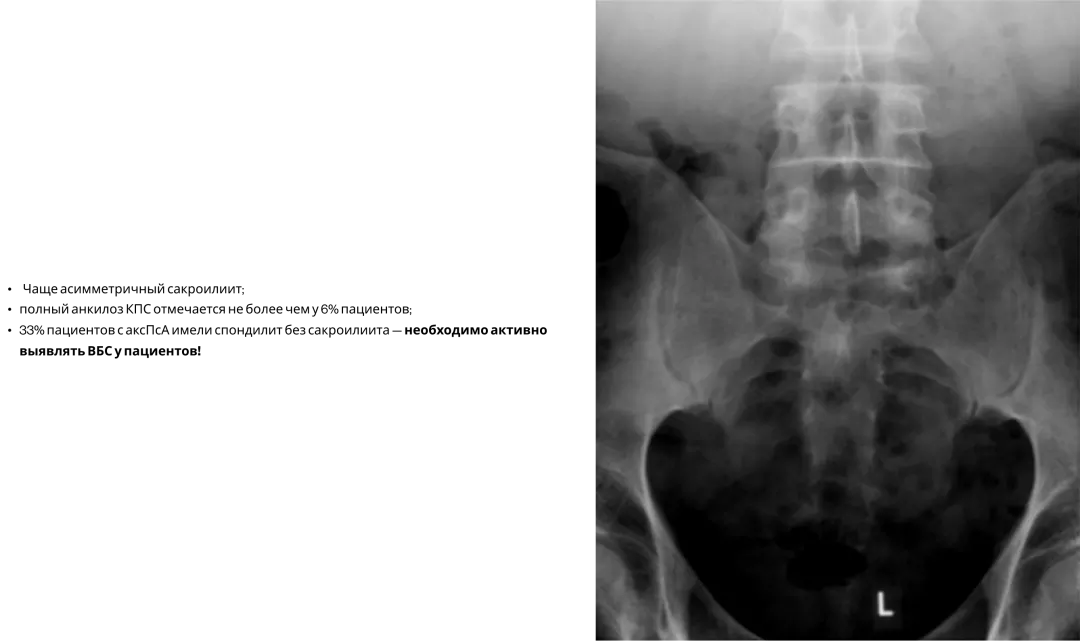

Сакроилиит при ПсА3

Сакроилиит при рентгенографии диагностируется примерно у 30% больных ПсА, при этом каждый четвертый (26%) пациент не жаловался на боль в спине. Поэтому наличие аксиальных поражений при ПсА необходимо активно выявлять3.

Image

Frame 24062083 (1).png

У пациентов с ПсА молчащий сакроилиит. Нужно активно выявлять ВБС!3,18